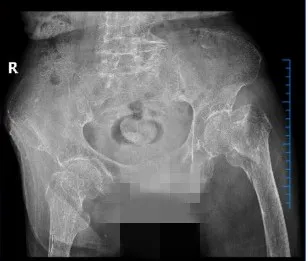

2025年3月,武寧(níng)縣總(zǒng)醫院人民醫院院區骨科團隊(duì)以精湛的技術和多學科協作模式,為一名(míng)104歲超高齡股骨粗隆間骨折(shé)患者成功實施微創(chuàng) Intertan 內固定術。這一壯舉不僅挽(wǎn)救了患者的生(shēng)命,更標誌著醫院在老年骨(gǔ)創傷救治領域取得了新的突破。

患者陳奶奶,今年104歲,因不慎跌倒導致左(zuǒ)側股骨粗隆間粉碎(suì)性骨折。她既往(wǎng)患有重度骨質疏鬆、低蛋白血症、心房(fáng)顫動、心功能不全、慢性阻塞性肺病(COPD)、脊柱畸形等多項基礎疾(jí)病。髖部(bù)骨折被稱為“人(rén)生最後(hòu)一次骨折”,保守治療會導致患者(zhě)長期臥(wò)床,不僅承受劇烈疼痛,還容易引發深靜脈血栓、肺部感染、褥瘡等嚴重並發症,死亡(wáng)率極高。